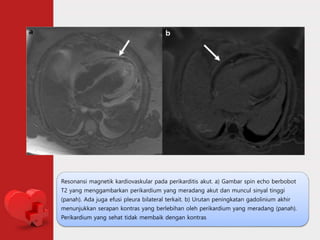

Resonansi magnetik kardiovaskular pada perikarditis akut. a) Gambar spin echo berbobot

T2 yang menggambarkan perikardium yang meradang akut dan muncul sinyal tinggi

(panah). Ada juga efusi pleura bilateral terkait. b) Urutan peningkatan gadolinium akhir

menunjukkan serapan kontras yang berlebihan oleh perikardium yang meradang (panah).

Perikardium yang sehat tidak membaik dengan kontras